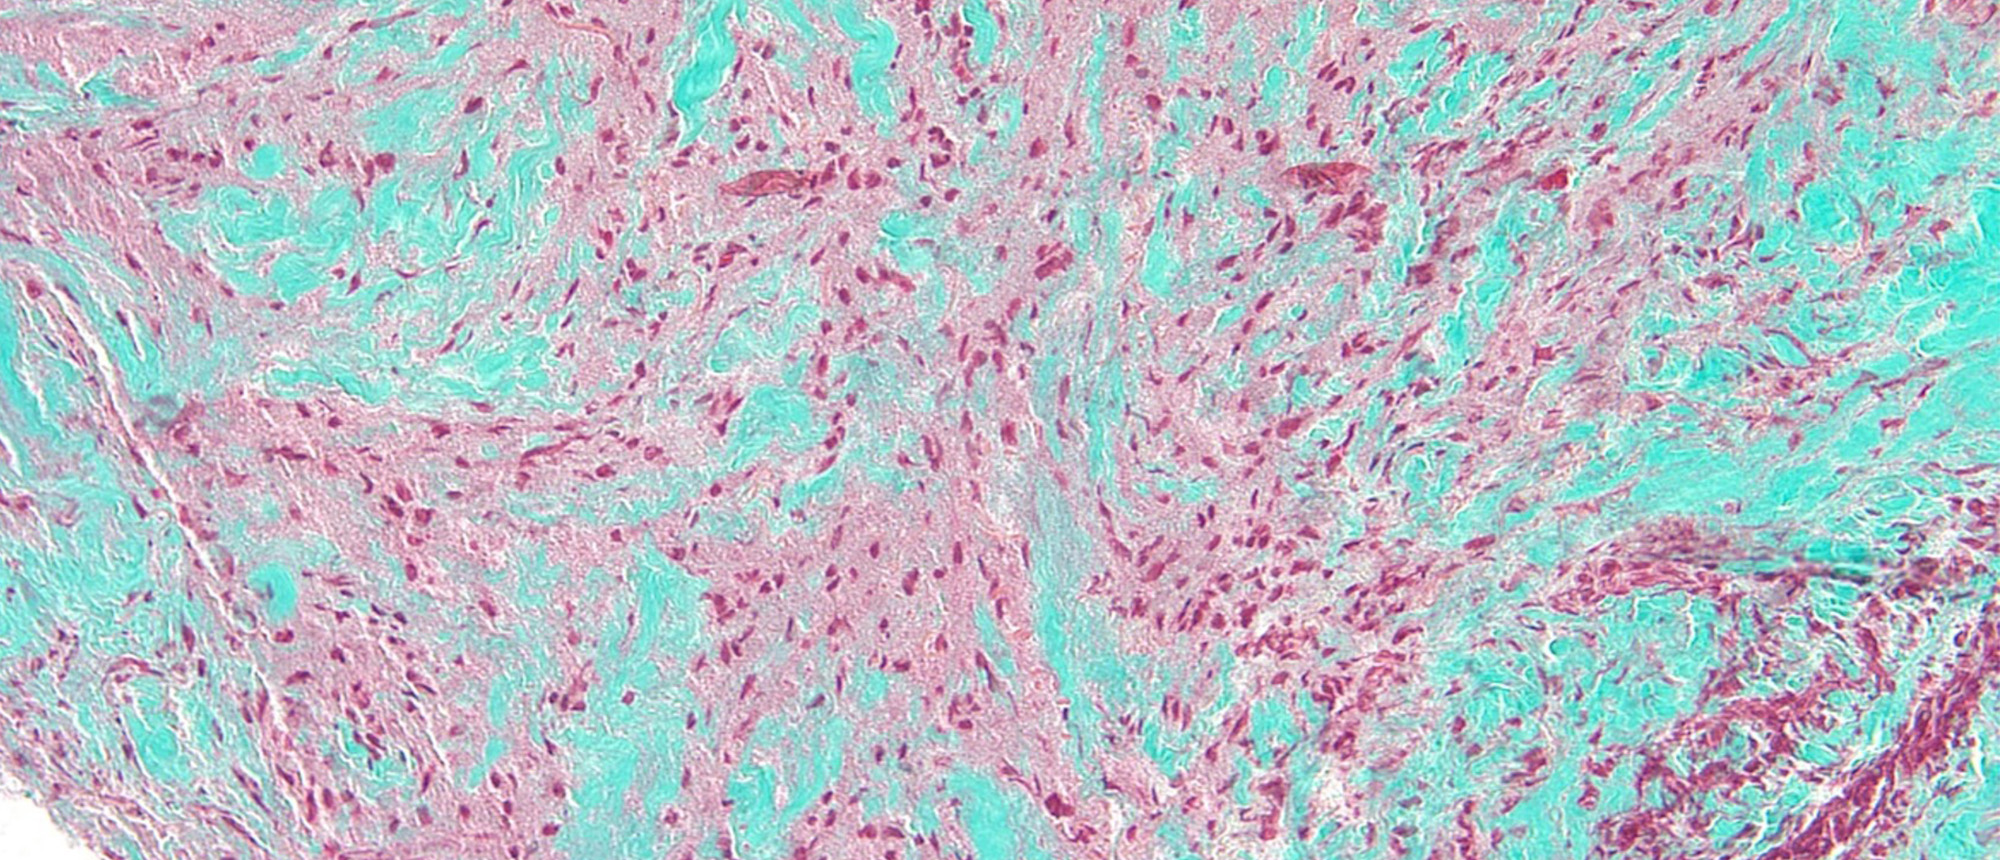

A patient with no past medical history and a past ocular history of five prior pterygium removal surgeries presented to the Bascom Palmer Emergency Room for pain and irritation in his right eye for 1 week. He endorsed working construction just prior to symptom onset, but denied any trauma to the ey…